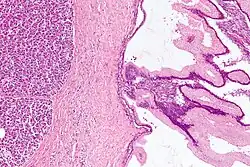

Rak gruczołowy przewodowy (barwienie H+E)

Na lewym zdjęciu śródnabłonkowa neoplazja trzustkowa niskiego stopnia i wysokiego stopnia. Na zdjęciu prawym rak trzustki

Śródnabłonkowa neoplazja trzustkowa jest najważniejszą zmianą przednowotworową prowadzącą do gruczolakoraka przewodowego trzustki. Prawdopodobnie większość przypadków raków inwazyjnych trzustki rozwija się na bazie śródnabłonkowej neoplazji[130][131].

Śródnabłonkowa neoplazja trzustkowa jest niewielką, nie przekraczającą 5 mm, płaską lub brodawkowatą bezobjawową zmianą wywodzącą się z małych przewodów trzustkowych[131][132]. Budują ją komórki od sześciennych do walcowatych wytwarzające mucyny, o atypii cytologicznej i architektonicznej różnego stopnia[132]. Jest ona klasyfikowana na trzy klasy o wzrastającym ryzyku raka inwazyjnego. Neoplazja niskiego stopnia (PanIN-1) wiąże się z minimalną atypią cytologiczną i architektoniczną, neoplazja umiarkowanego stopnia (PanIN-2) z umiarkowaną atypią cytologiczną i architektoniczną, a neoplazja wysokiego stopnia (PanIN-3) z nasilonymi zmianami cytologicznymi i architektonicznymi[132]. PanIN-1A jest płaską zmianą zbudowaną z nabłonka walcowatego z jednorodnymi okrągłymi lub owalnymi jądrami komórkowymi. PanIN-1B to zmiana brodawkowata i morfologicznie podobna do PanIN-1A. W PanIN-2 stwierdza się utratę polarności jądra komórkowego, pseudowielorzędowość, stłoczenie jąder komórkowych, pleomorfizm wielkości jąder komórkowych oraz hiperchromazję jąder komórkowych. PanIN-3 wykazuje znaczną atypię architektoniczną i komórkową, występują struktury brodawkowate lub przypominające sito, mogą występować zgrupowania komórek w świetle przewodów. Komórki posiadają powiększone, pleomorficzne jądro, dochodzi do utraty polarności jądra komórkowego. Mogą być widoczne figury mitotyczne, a nawet nieprawidłowe mitozy[133].